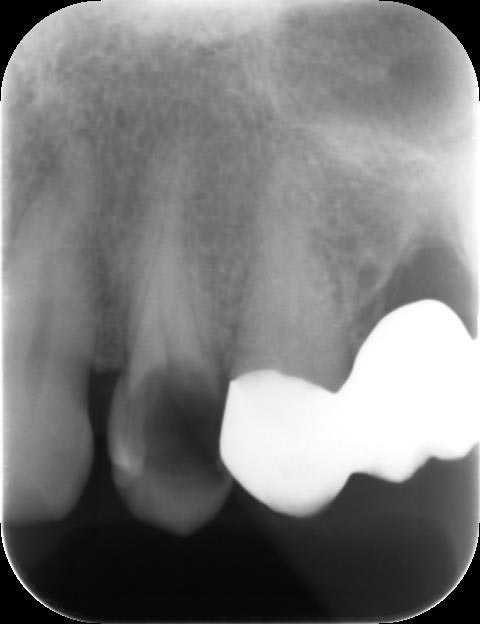

とても大きいむし歯です。まずは、歯髄が生きているかを調べます。

電気歯髄診断と呼ばれる方法で生活反応がありました。

患者さんご自身でも、今までに痛くなったことはないと言っていました。

レントゲン写真でも大きなむし歯のような歯の欠損を認めるものの、根の先や周囲には影などはありませんでした。総合的に歯髄を残せると判断しました。